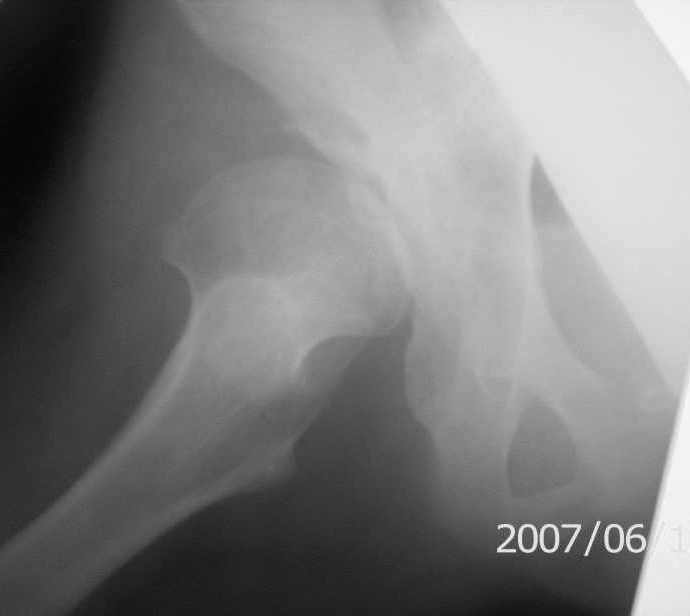

On x-rays coxa magna, shallow true + pseudoacetabulum.Options: salvage

Ацетабулюм крайне недоразвит. Есть высокий подвывих, можно даже сказать вывих с формированием ложного ацетабулюм. Для головки нет покрытия совсем и расположена она высоко.

На мой взгляд - SHORTENING OSTEOTOMY , VARUS если надо (на основании снимка во внутренней ротации), репозиция головки, CHIARI OSTEOTOMY или SHELF OPERATON Спасибо за интересный случай.